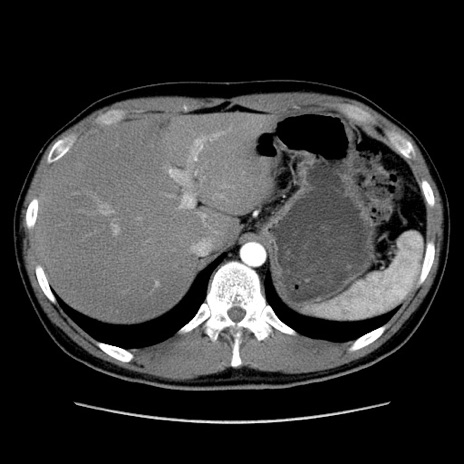

症例36(横断像)

【症例】20歳代 男性

【主訴】心窩部痛

【現病歴】今朝より上腹部痛あり。一旦軽快していたが再度出現したため救急要請。昨日夕に白身の魚を含む刺身を食べた。

【身体所見】BP 136/89mmHg、HR 74/min、BT 37.0℃、腹部:膨満、軟、心窩部に圧痛あり。反跳痛なし、筋性防御なし、腸雑音やや亢進あり。

【データ】WBC 17700、CRP 0.48